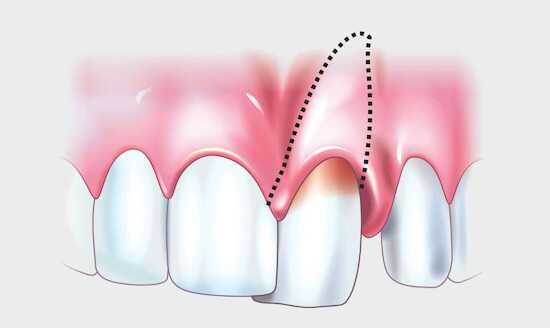

Металлические коронки. Установка классических металлических коронок имеет такой дефект, как потемнение зуба в зоне краевой линии десны. Появление черноты свидетельствует о процессе окисления, который вызывает воздействие кислотной среды полости рта на металл.

Пульпит, периодонтит

Воспаление нерва или корня сопровождается острой болью. Своевременное лечение, вероятно, поможет избежать потемнения поражённого зуба. Однако хроническая форма патологии приведёт к отмиранию сосудисто-нервного пучка, из-за чего ткани зуба потемнеют.